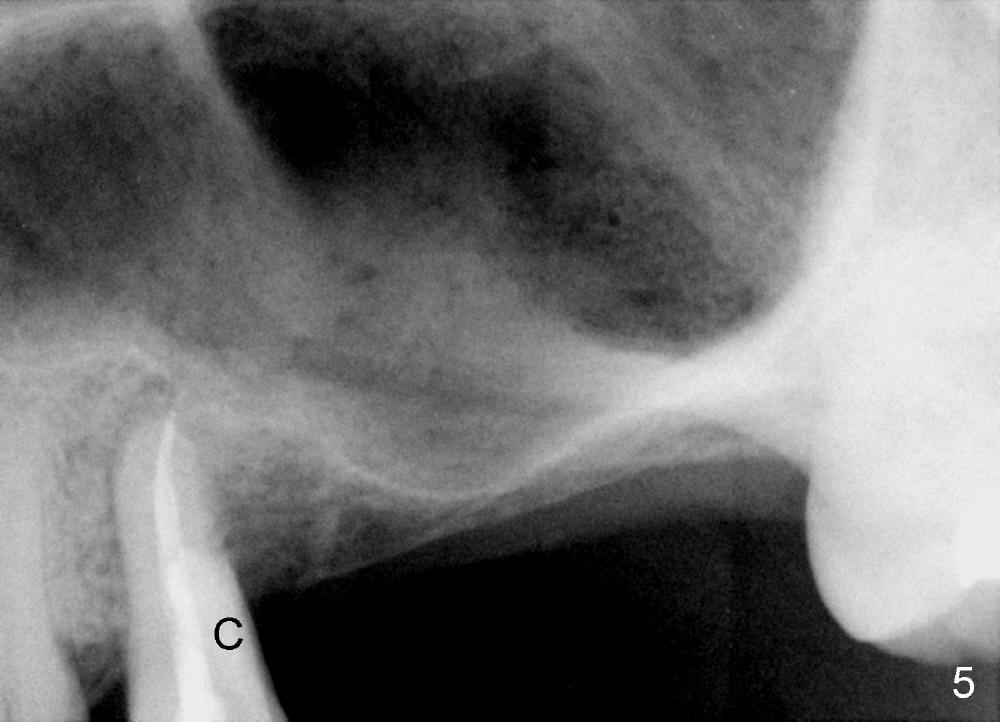

After local anesthesia and rubber dam isolation, caries is removed from the distal cervical region. Access is provided occlusally. Initial debridement is done with hand files until #20 with copious irrigation with 3% sodium hypochlorite. The shortcoming is bleach leakage. While #15 and 20 files are inserted in the buccal and lingual canals, the distal cavity is filled with Cavit temporarily. There is no more leakage, while the canals remain patent. RCT is finished with ease (Fig.4). Then the distal cervical Cavit is removed, followed by routine composite build up (Fig.5 C). The patient remains asymptomatic for 2 months now.